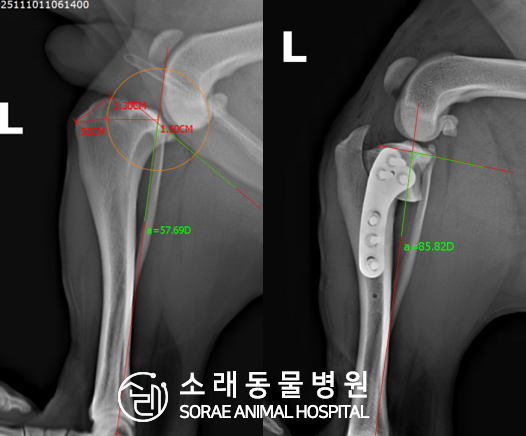

계산식으로 사전에 계획해두었던 플랜에 따라 경골을 절제하고

플레이트와 스크류를 사용하여 임플란트를 적용해 주었습니다.

반대 방향으로 밀려나 어긋나있던 대퇴골과 정강이가

제 자리를 찾으면서 무릎의 각도가 교정된 것을 확인할 수 있습니다